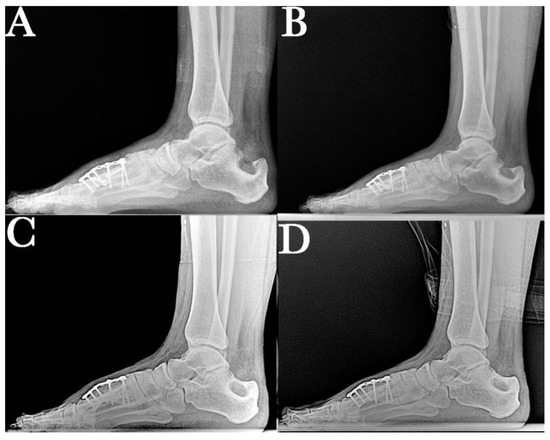

1. Introduction

2. Case Report

2.1. Surgical Procedure

2.2. Postsurgical Procedure and Evolution

2.3. Results